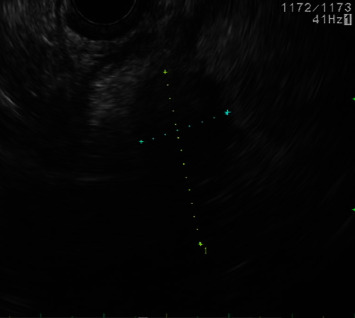

髓系肉瘤(MS)是急性髓系白血病(AML)的髓外表现,通常发生在淋巴结、皮肤、软组织和骨骼等部位。在胰腺中的表现更为罕见,自1987年以来,文献报道的病例不足20例。尽管 MS 很罕见,但在鉴别诊断引起阻塞性黄疸的软组织肿块时应考虑 MS,尤其是当患者患有已知的血液病时。已知胰腺多发性硬化的孤立病例可发展为急性髓细胞性白血病;因此,将多发性硬化与胰腺癌或胰腺炎等更常见的诊断相鉴别至关重要。这是一例 70 岁男性因胰腺多发性硬化继发症状性梗阻性黄疸的病例,最终需要通过内镜超声(EUS)和内镜逆行胰胆管造影(ERCP)进行诊断和治疗。该报告还全面回顾了以往类似胰腺多发性硬化症的临床表现、管理和治疗的病例报告。

Myeloid sarcoma (MS) is an extramedullary manifestation of acute myeloid leukemia (AML) and commonly occurs in sites such as the lymph nodes, skin, soft tissues, and bone. It more rarely manifests in the pancreas, with less than 20 cases reported in the literature since 1987. Despite its rarity, MS should be considered in the differential diagnosis of a soft tissue mass causing obstructive jaundice, especially if the patient has a known hematologic disease. Isolated cases of pancreatic MS have been known to progress to AML; therefore, it is crucial to differentiate MS from more common diagnoses, such as pancreatic cancer or pancreatitis. This is a case of a 70-year-old male with symptomatic obstructive jaundice secondary to pancreatic MS, ultimately requiring endoscopic ultrasound (EUS) and endoscopic retrograde cholangiopancreatography (ERCP) for diagnosis and management. Also included is a comprehensive review of previous case reports with similar clinical presentations, management, and treatment of pancreatic MS.